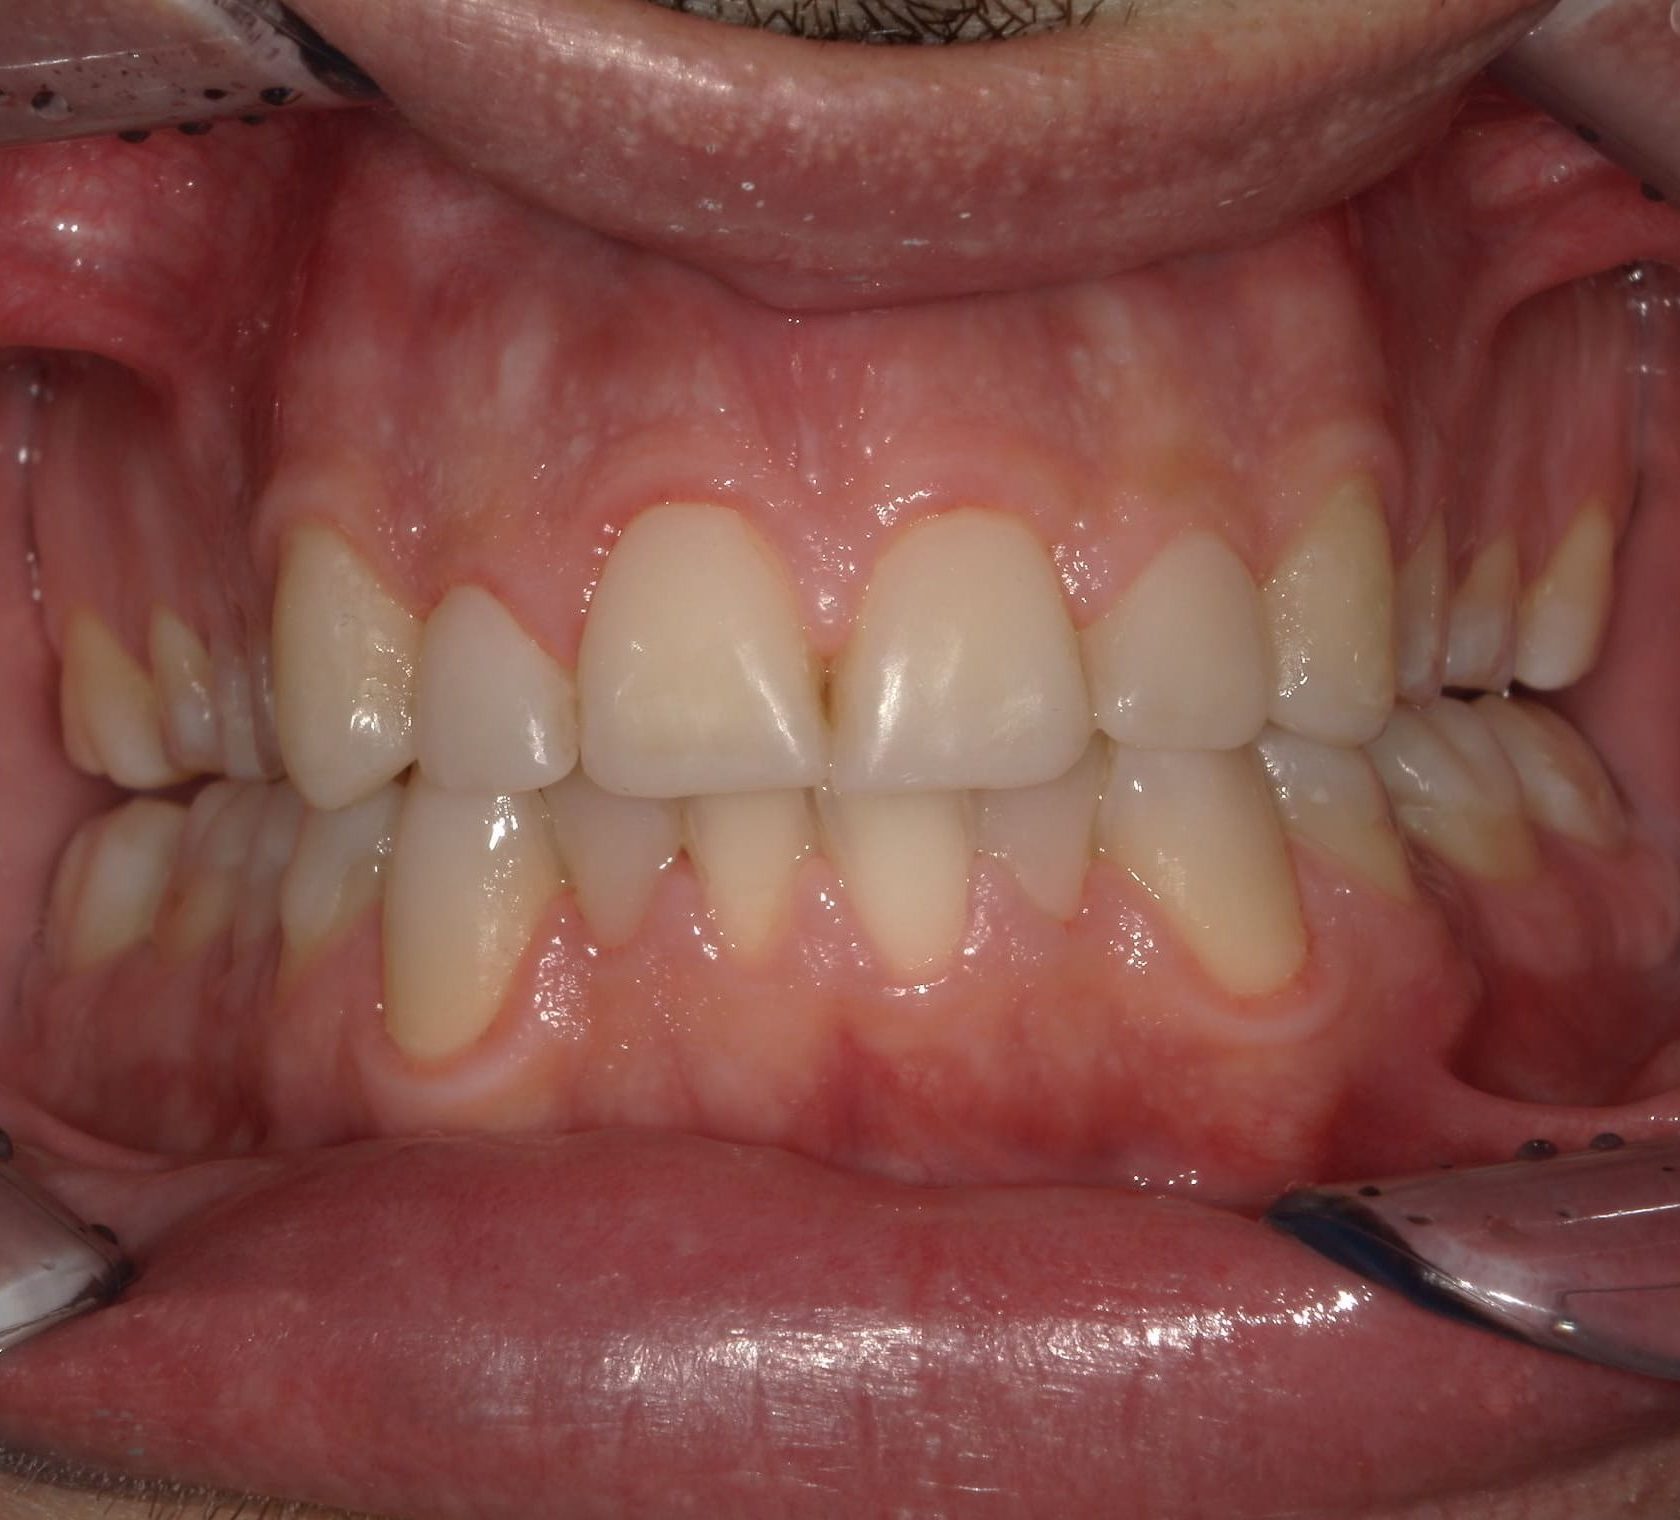

Prima

Dopo